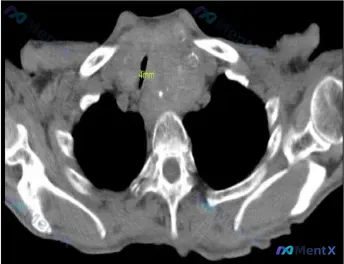

病例核心影像与事实

- 甲状腺大小:左侧约 79 x 65 mm,右侧约 64 x 41 mm;

- 气道评估:气管明显向右移位,最窄处直径仅 4 mm;

- 软组织特征:颈部及胸廓入口处大片软组织影,形态不规则,边界不清,包绕/推挤周围结构;内部可见点状高密度钙化影;

- 周围结构:周围大血管走行受干扰/挤压,解剖结构紊乱;椎体骨质未见明确破坏,但软组织影紧贴椎前。